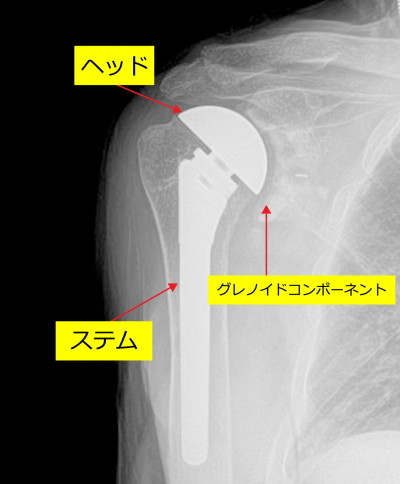

【人工関節置換術】

人工関節置換術は以下のイラストのような器具を、肩の肩甲骨と上腕骨に挿入します。イラストをみてください。変形した上腕骨に金属のボール(ヘッド)と芯棒(ステム)を上腕骨に、肩甲骨の関節窩というところにプラスチックの受け皿(イラスト右、グレノイドコンポーネント)を設置します。プラスチックの受け皿は一般的には骨セメントという接着剤で固定します。

下の図はその人工関節が上腕骨と肩甲骨にはいった状態を示しています。ステムとヘッドは連結しています。

下の図はプラスチックの受け皿(プラスチックコンポーネント、医師はグレノイドコンポーネントと呼んでいます)が肩甲骨関節窩に挿入された状態を示しています。

手術後のレントゲン

上腕骨の変形した骨頭を切除し、肩甲骨にもプラスチックの受け皿が入っています。